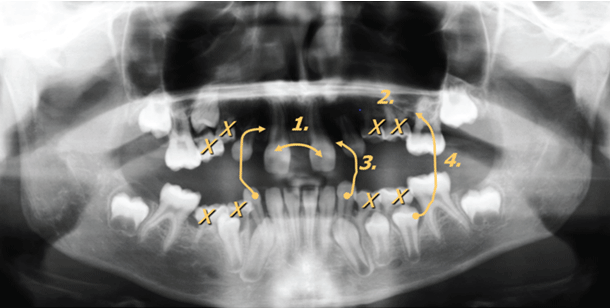

一个10岁的患者在象限II提到我们通过她的正畸医生进行咨询,由于在总(图1A-1C)与缺乏象限我三个恒牙的八颗牙齿发育不全,四个恒牙,一恒牙在象限IV,且不乏象限III。由于患者在在预约的时间年轻时是,主齿73和83仍然存在(图1C)。由于在上钳口(N = 7)的大量缺失牙齿的,我们决定于以下正畸手术的概念,它包括以下四个主要措施(图2):

图2:正畸和手术规划(详细介绍文字)